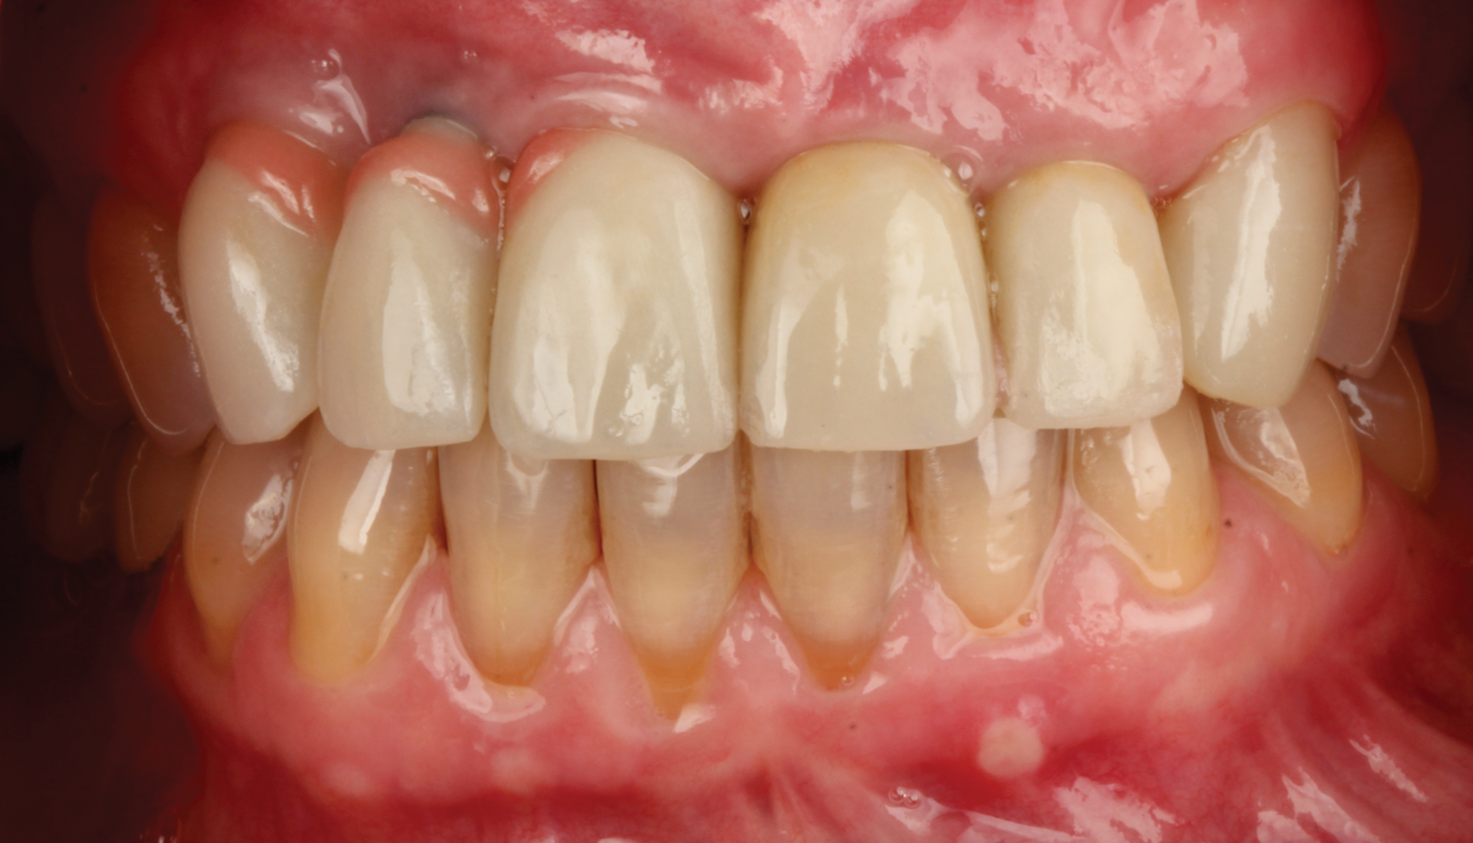

A middle-aged female patient presented with a severely damaged maxillary dentition due to traumatic injury (Figure 1). Ordinarily, this treatment would be planned to splint multiple adjacent implants for optimal mechanical strength and load distribution.7 However, in this case the patient specifically requested an independent implant for each single tooth (sites Nos. 6 through 10), as she previously had had poor experiences with bridged restorations and strongly desired to be able to maintain the restorations in a manner that was as close to natural, single teeth as possible without needing any adjunctive maintenance protocols due to splinting of restorations. Although this option is not typically recommended because of the challenges it poses in execution of therapy from an esthetic perspective, the clinician agreed to this approach to satisfy the patient's desires. The treatment was thus digitally planned accordingly.

Five individual screw-retained milled ceramic crowns completed the all-digital treatment used to restore the patient without complication. As indicated in photographs taken at delivery of the final prostheses, the wholly digitally planned and executed restoration achieved a completely technological, natural-appearing outcome, and the patient was extremely satisfied (Figure 6).

Fig 1. Case 1, initial situation at presentation.

Figure 1

Fig 6. Final outcome at delivery of screw-retained milled ceramic crown restorations.

Figure 6